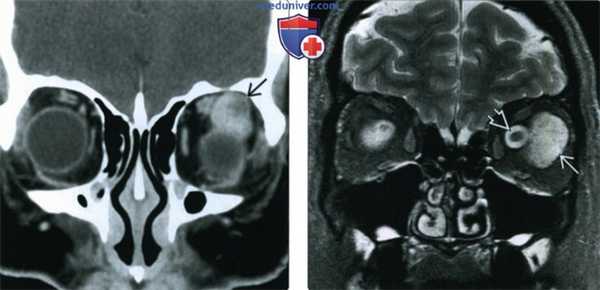

(Слева) При КТ с КУ в корональной проекции внутри мышечного конуса определяется объемное образование; наблюдается раннее «лоскутное» контрастирование, что с высокой вероятностью указывает на кавернозную мальформацию глазницы. Хотя образование простирается к периферии глазницы, его центр лежит внутри мышечного конуса.

(Справа) При STIR MPT внутри мышечного конуса определяется крупная кавернозная мальформация. Образование дает интенсивный сигнал, аналогичный сигналу спинномозговой жидкости, окружающей смещенный зрительный нерв.